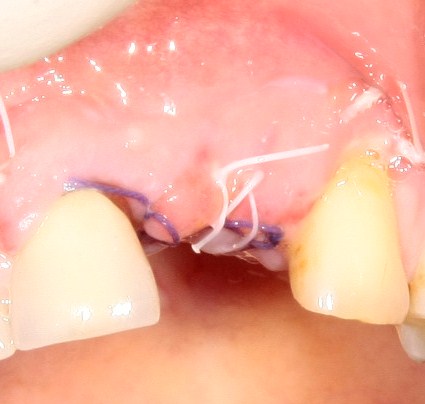

После чего накладываем швы. В местах сильного натяжения я не полагаюсь на Gore-Tex, прошиваю их толстым (4-0) Викрилом. Но лучше ВСЕГДА использовать нерезорбируемый шовный материал.

Вот так она выглядит через два дня:

А вот так — через четыре:

Уже на этом этапе можно сказать, что дальнейший послеоперационный период пройдет без проблем — пациентку ничто не беспокоит, цвет и состояние слизистой оболочки в области швов вполне себе нормальное. А это значит, что первый этап закончится успешно.